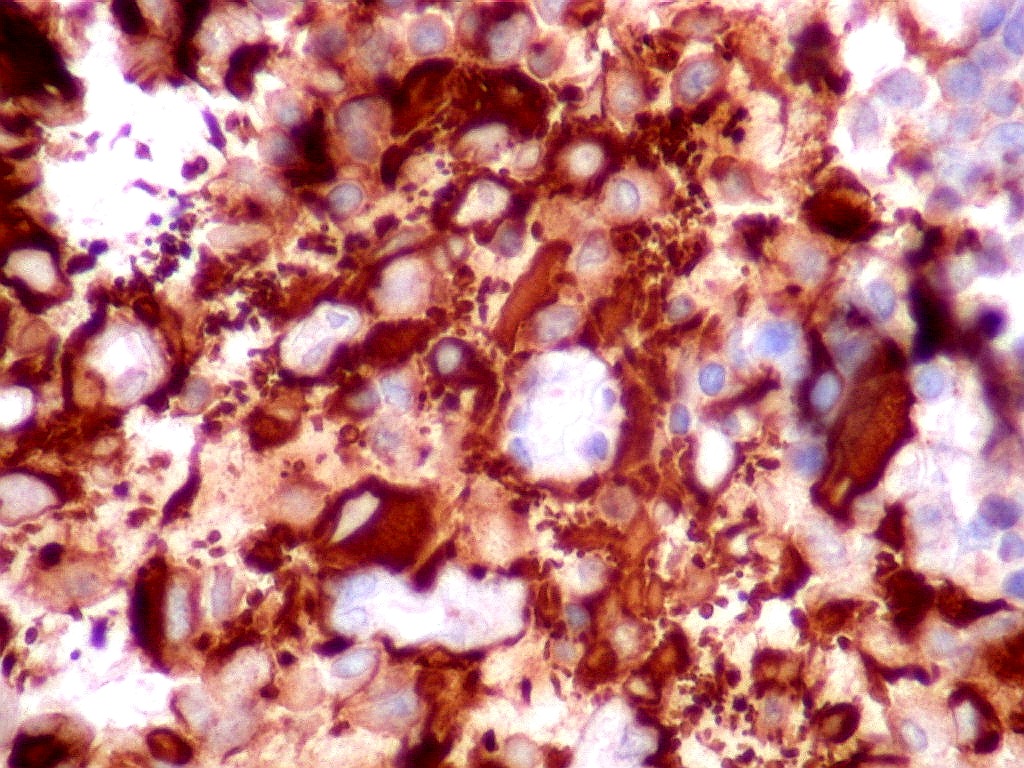

Tumor teratóide rabdóide atípico de III ventrículo.

2. Vimentina, GFAP.

GFAP.     O filamento intermediário do citoesqueleto que caracteriza os astrócitos é forte e difusamente positivo nas células neoplásicas deste tumor teratóide-rabdóide atípico.  Indica diferenciação astrocitária no tumor.  O folículo linfóide e vasos proliferados são negativos.  O epêndima  do III ventrículo, onde o tumor está localizado, também é GFAP positivo.